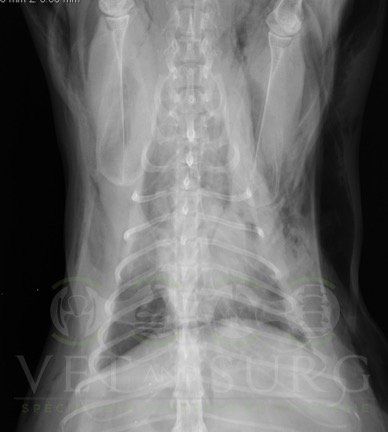

Thoracique

Dans la gestion des pathologies respiratoires, cardio-vasculaires, et des atteintes médiastinales et diaphragmatiques.